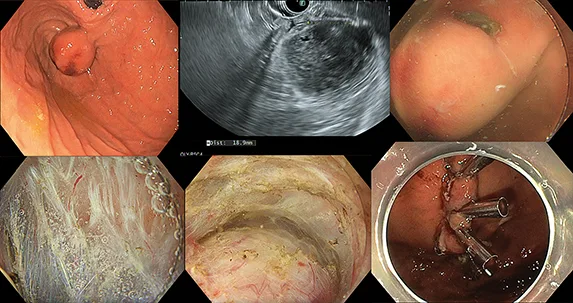

Figure 2 : Résection par FTRD d’une GIST gastrique de 15 mm

Tumeur sous-muqueuse peu bombante, connectée à la couche musculaire propre (4e couche), réséquée par technique hybride : ESD avec excavation puis EFTR à l’aide d’un clip OVESCO